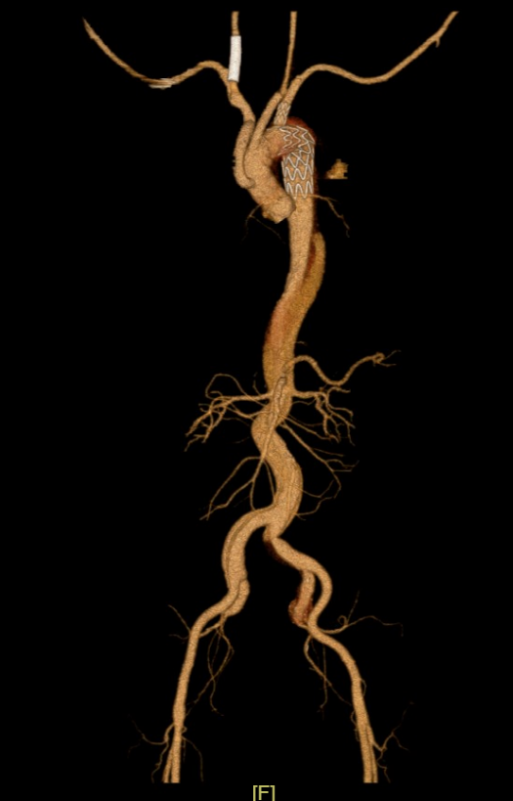

△右颈总动脉术前术后对比

△主动脉夹层术前术后对比

第一步,脑血管科团队马上为患者行“脑血管造影+颈动脉支架置入术”。第一步的枢纽难点在于:传统经股动脉入路时,导丝在主动脉夹层内难以准确参加主动脉真腔,操气派险高、胜仗率低。经多学科团队充分评估商议后,脑血管科改革性遴荐经肱动脉入路,经锁骨下动脉参加主动脉,在导丝交流下得手参加真腔。

在此基础上,进一步卓越长节段夹层,精确参加右侧颈总动脉真腔,植入支架建造血管内膜扯破,胜仗复原脑部血流,昭彰改善脑低灌输景况,为后续主动脉夹层外科手术创造了安全条目,获取了可贵的时代窗口,也为患者神经功能的复原奠定了基础。

第二步,在脑血流知道明,腹黑外科团队奋力上台,为患者执行主动脉夹层A型外科手术。A型主动脉夹层手术是腹黑外科规模难度最高、风险最大的手术之一,需在深低温停轮回下切除病变血管、置换东谈主工血管,操作复杂、耗时漫长,敌手术团队的技巧水和善配合默契度齐是极限试验。在麻醉科、体外轮回团队的紧密配合下,腹黑外科团队凭借深湛技巧,得手完成主动脉置换,胜仗拔除体内“炸弹”。